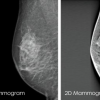

• At Auckland Breast Centre we use 3D mammography technology called Tomosynthesis.  Tomosynthesis delivers high-quality images resulting in more reliable diagnoses and will take 30 seconds per breast at the same time as the mammogram.  While the mammogram is being taken, each breast will be compressed between two flat plates on the x-ray machine.